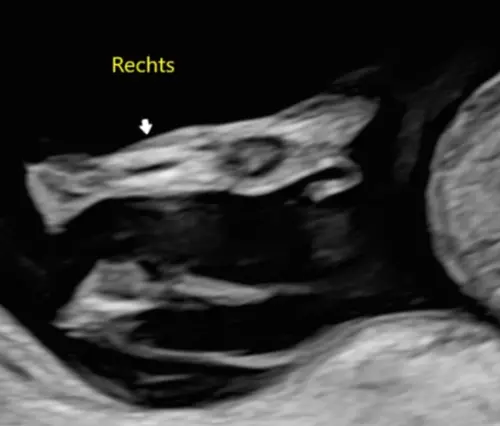

Ik heb gisteren een geslachtsecho gehad met 16 weken, het is een jongetje alleen heb ik het gevoel dat het aanzicht vanaf de bovenzijde is? Klopt dit?😋

Nee dit is onder het kontje zicht, dit is zeker weten een jongen😊

Dit is de potty shot die ik heb, zien wij het echt goed ? Het is nog een beetje moeilijk te bevatten 😆